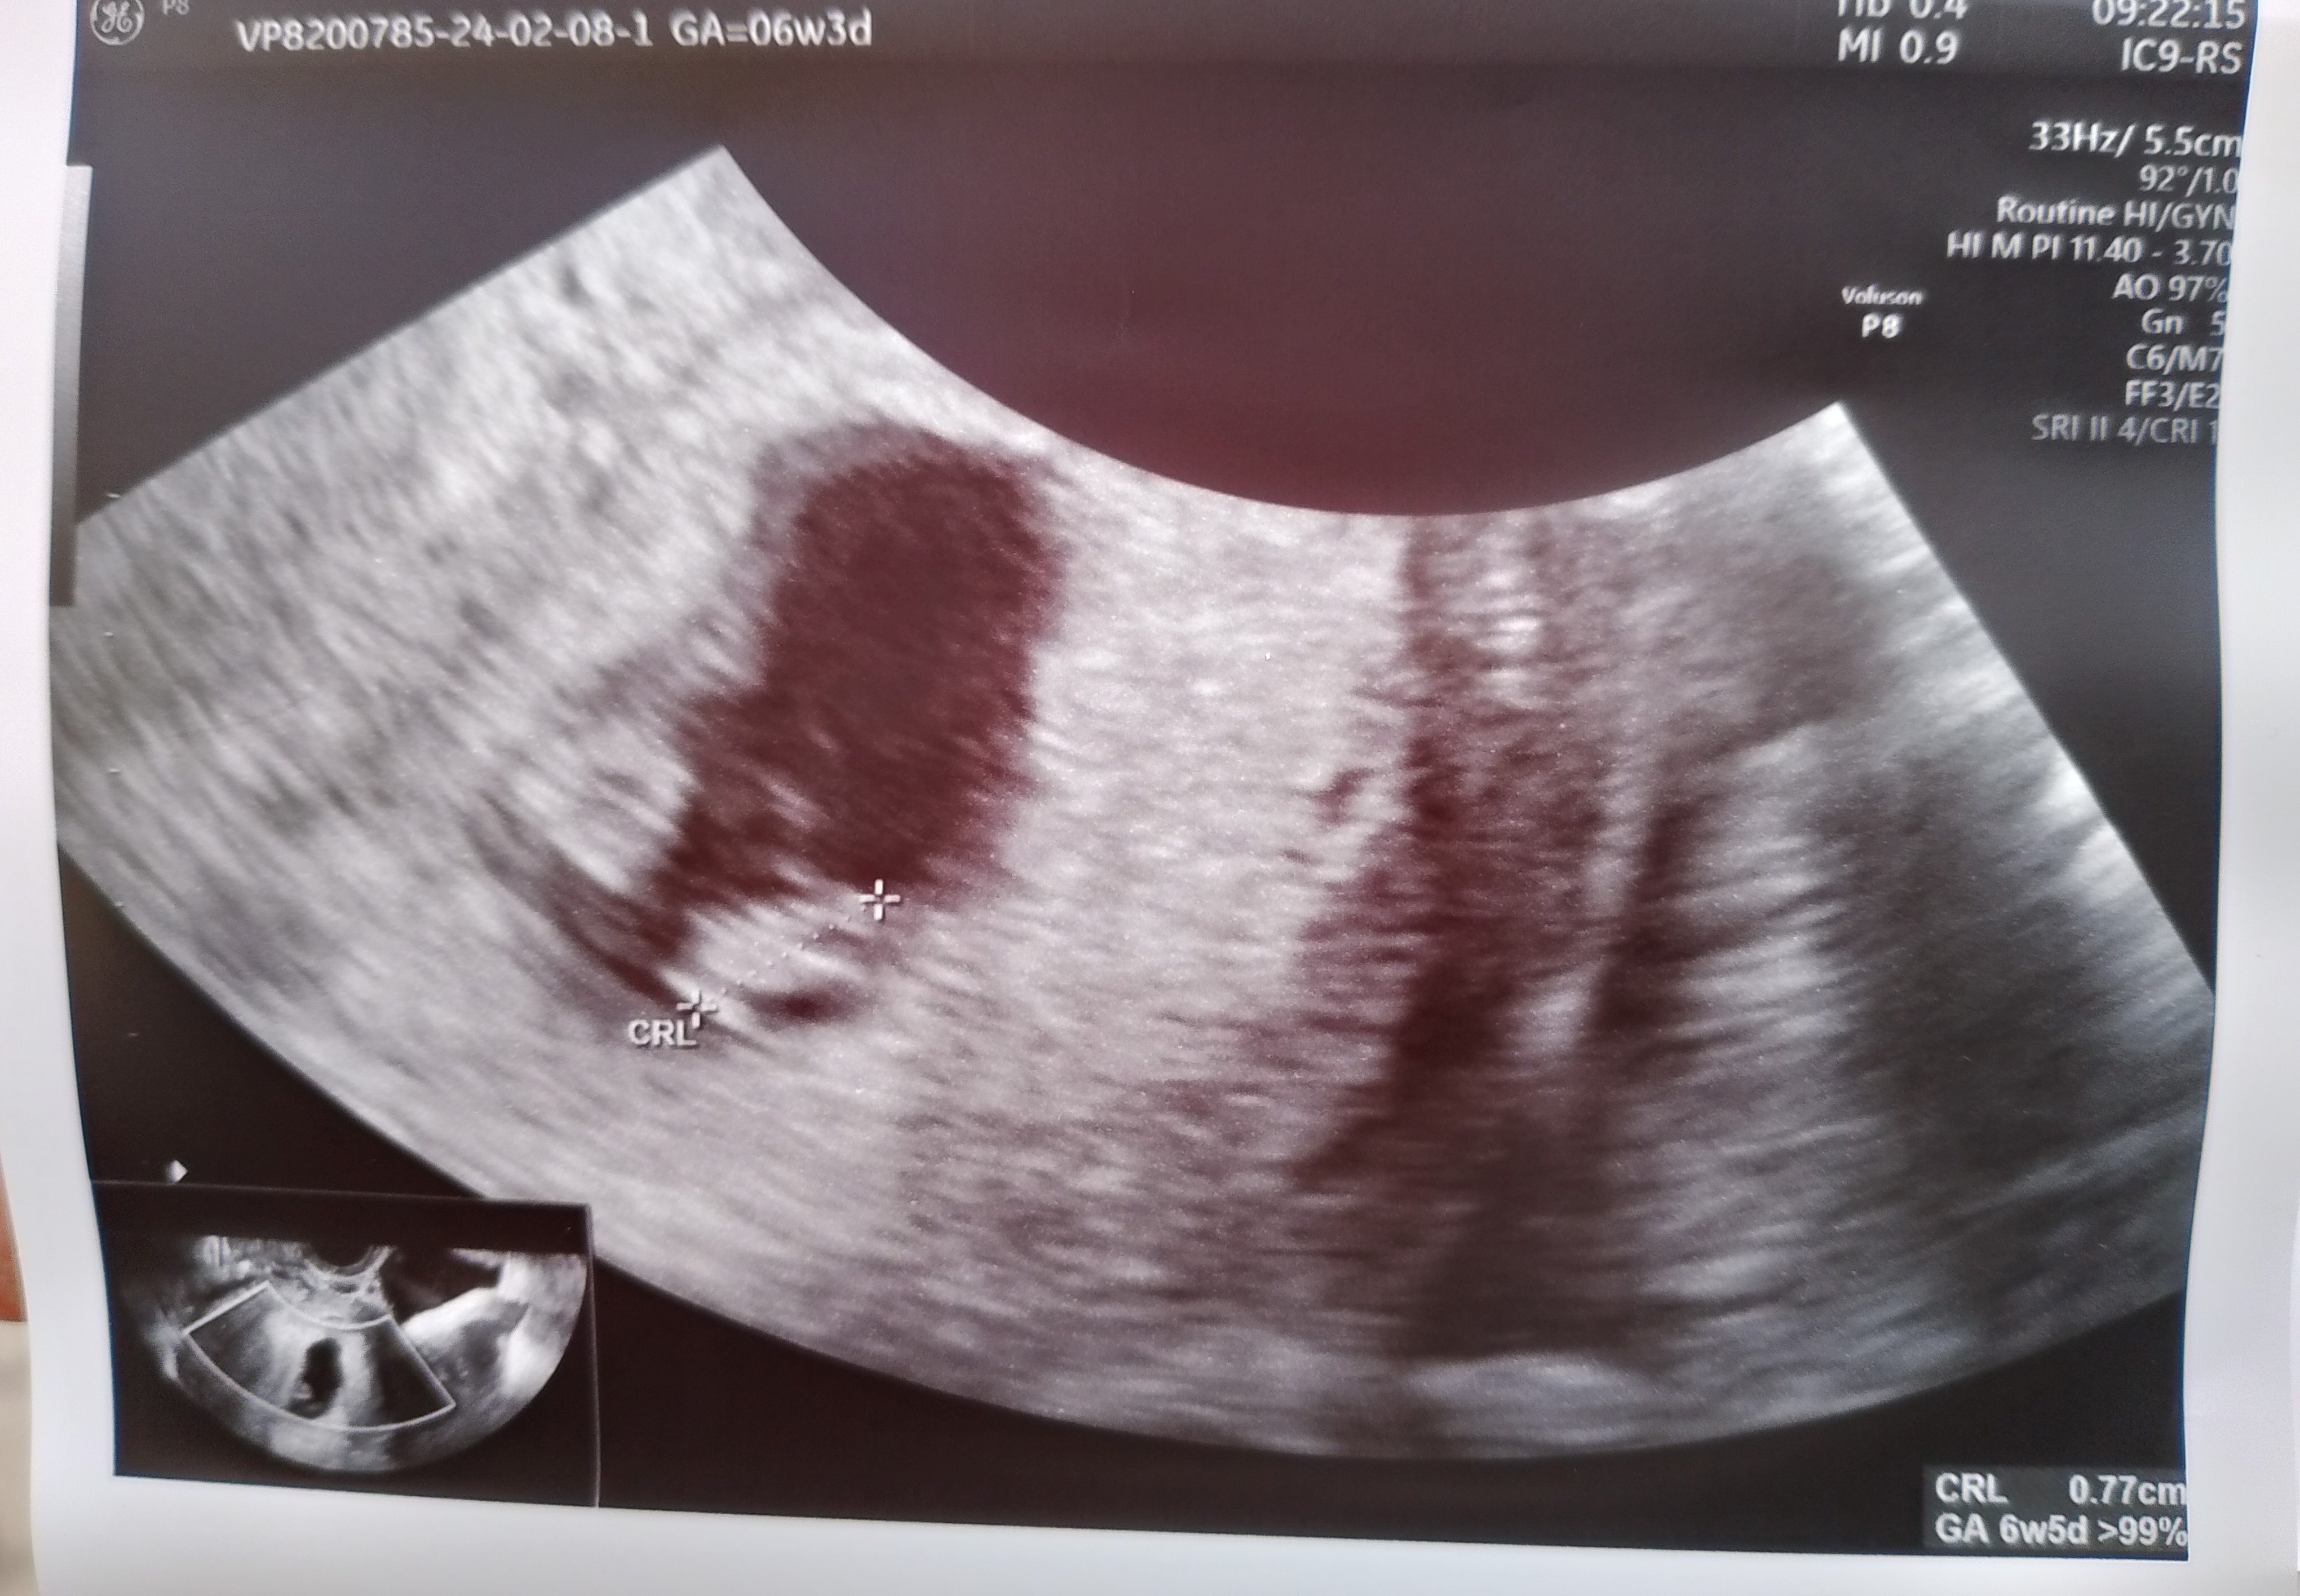

Piękny maluszekWitajcie , jestem po wizycie

6+3 wg OM

6+5 wg USG

Maluszek 7,7 mm

Serduszko bije